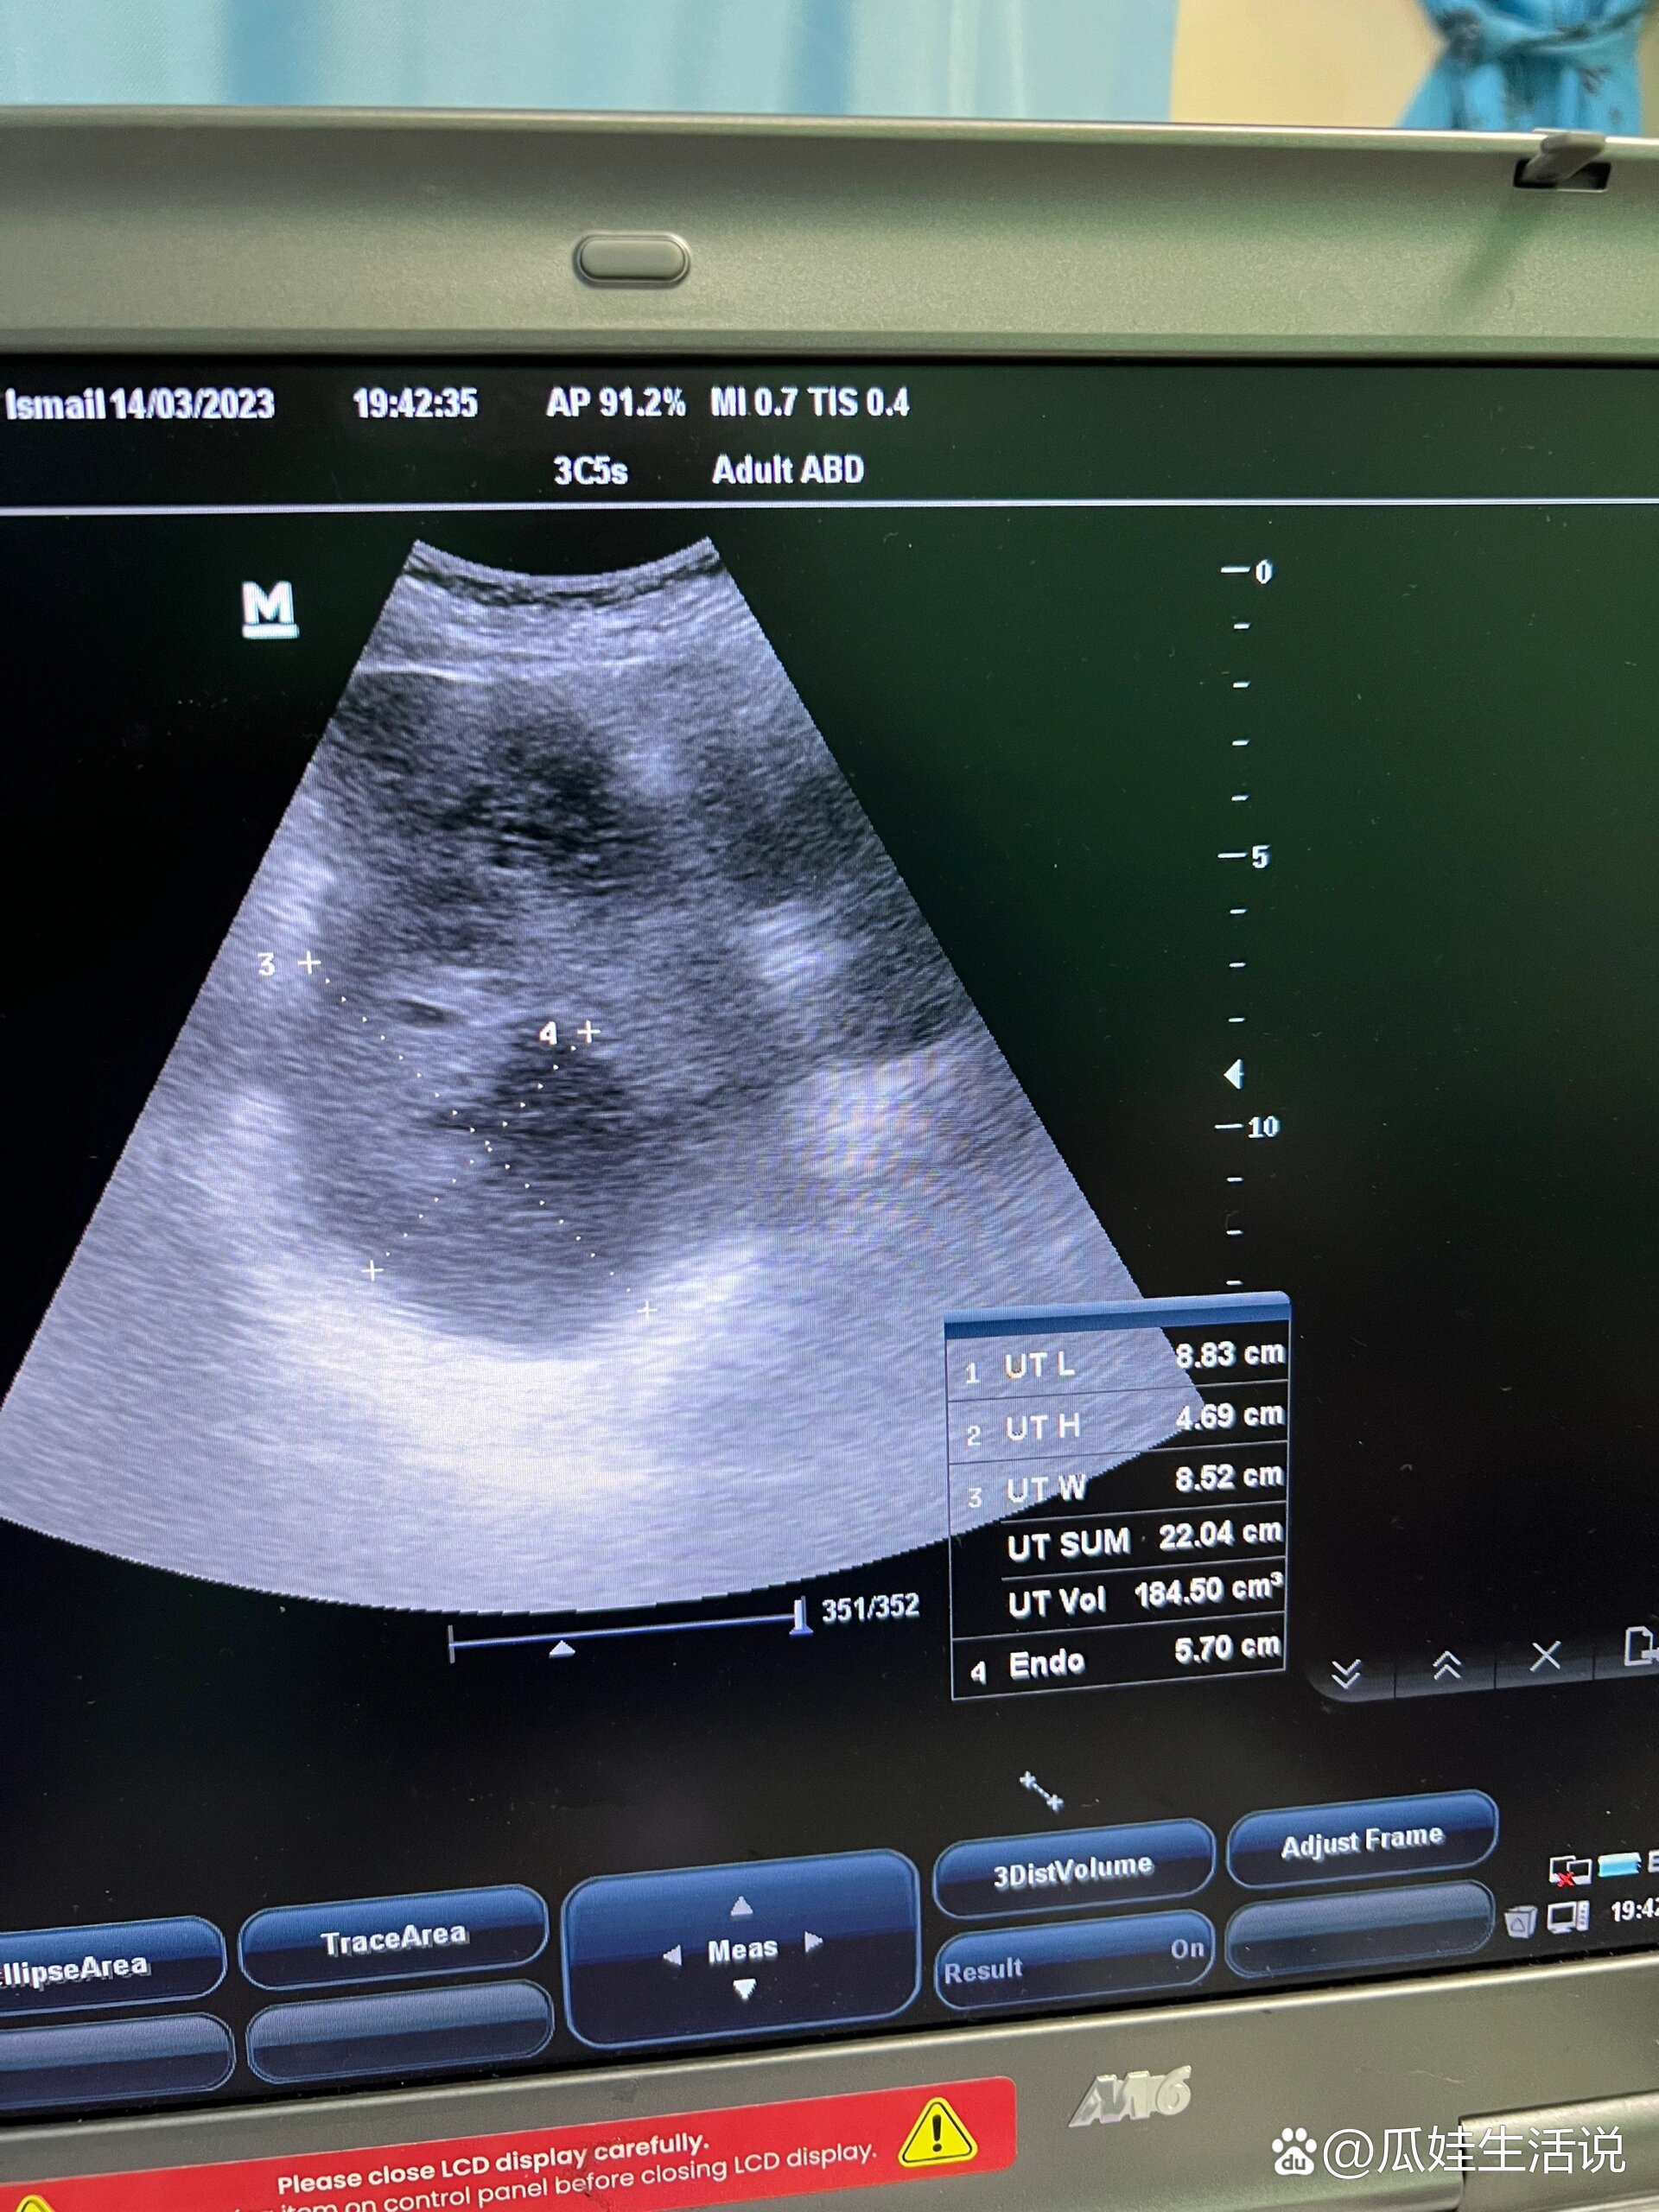

4、在北京大学肿瘤医院和中国医学科学院肿瘤医院的甲状腺结节就诊经历主要包括以下几点确诊过程在北京大学肿瘤医院,经过一系列检查,包括甲状腺B超穿刺等,最终确诊为良性结节在中国医学科学院肿瘤医院,也进行了多次B超检查,观察结节的变化情况病情观察在中肿的多次B超观察中,发现右边的甲状腺小结节。